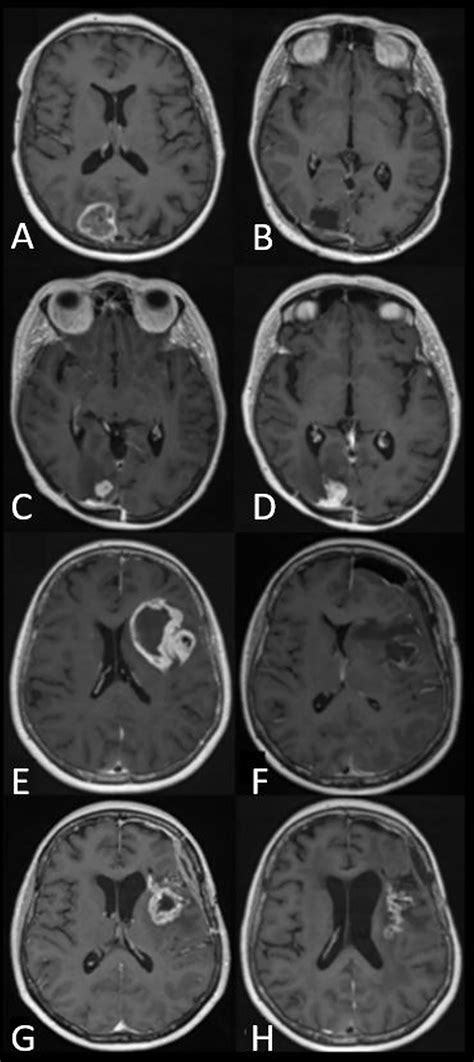

The journey toward a formal diagnosis usually begins with a neurological examination followed by advanced imaging. Physicians rely on several diagnostic tools to map the tumor’s size, location, and relationship to vital brain structures. Magnetic Resonance Imaging (MRI) with contrast remains the gold standard for visualizing these growths. In many cases, specialized sequences such as spectroscopy or perfusion imaging are used to differentiate between tumor tissue and postoperative changes.

The primary objective is maximal safe resection. Surgeons utilize neuronavigation systems and intraoperative MRI to remove as much of the tumor as possible. Even when total removal isn’t possible, “debulking” the tumor can alleviate intracranial pressure and improve the efficacy of subsequent therapies.

• high grade glioma MRI